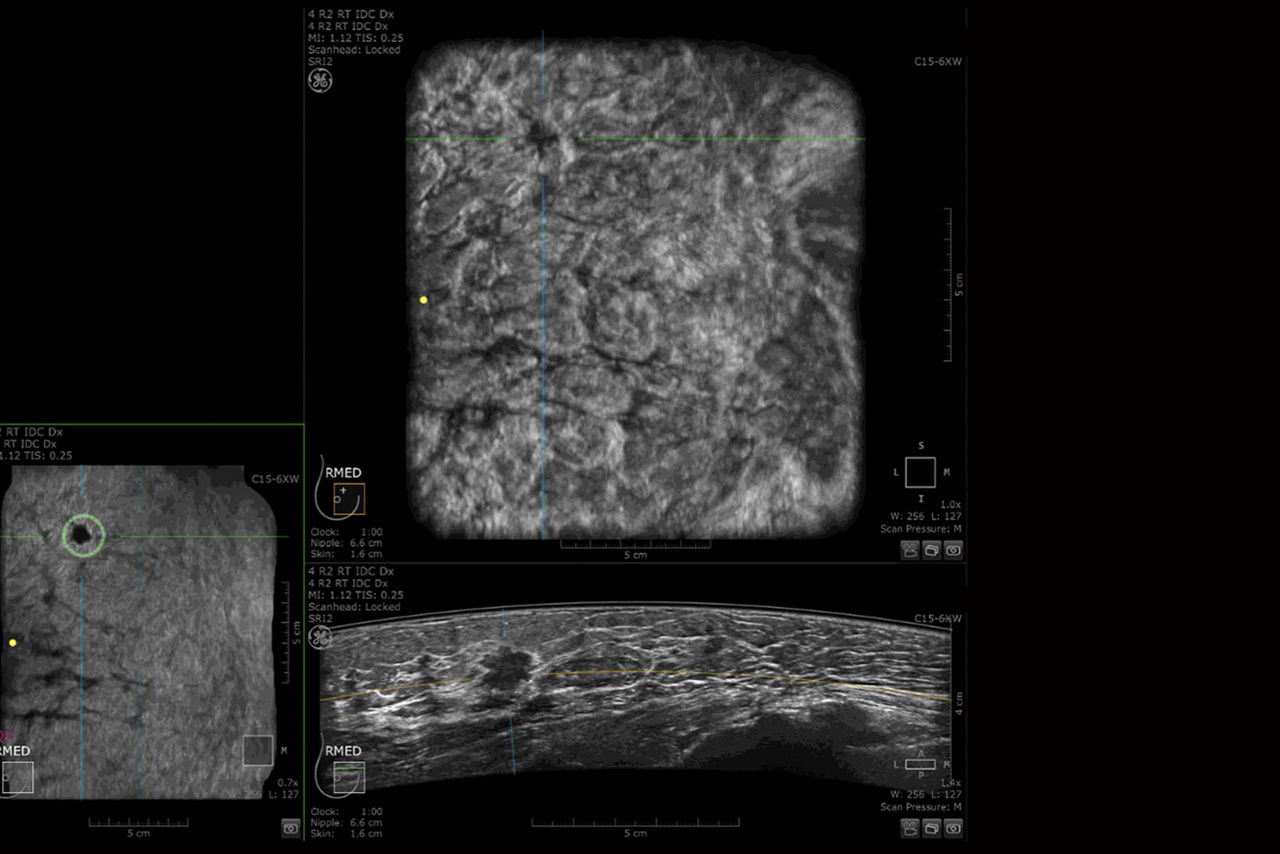

TREATMENT

Smart surgical planning

Invenia ABUS 2.0 provides a full view of the breast, depicting the extent of the lesion, multiplicity and potential stromal involvement, helping to achieve a better surgical approach.